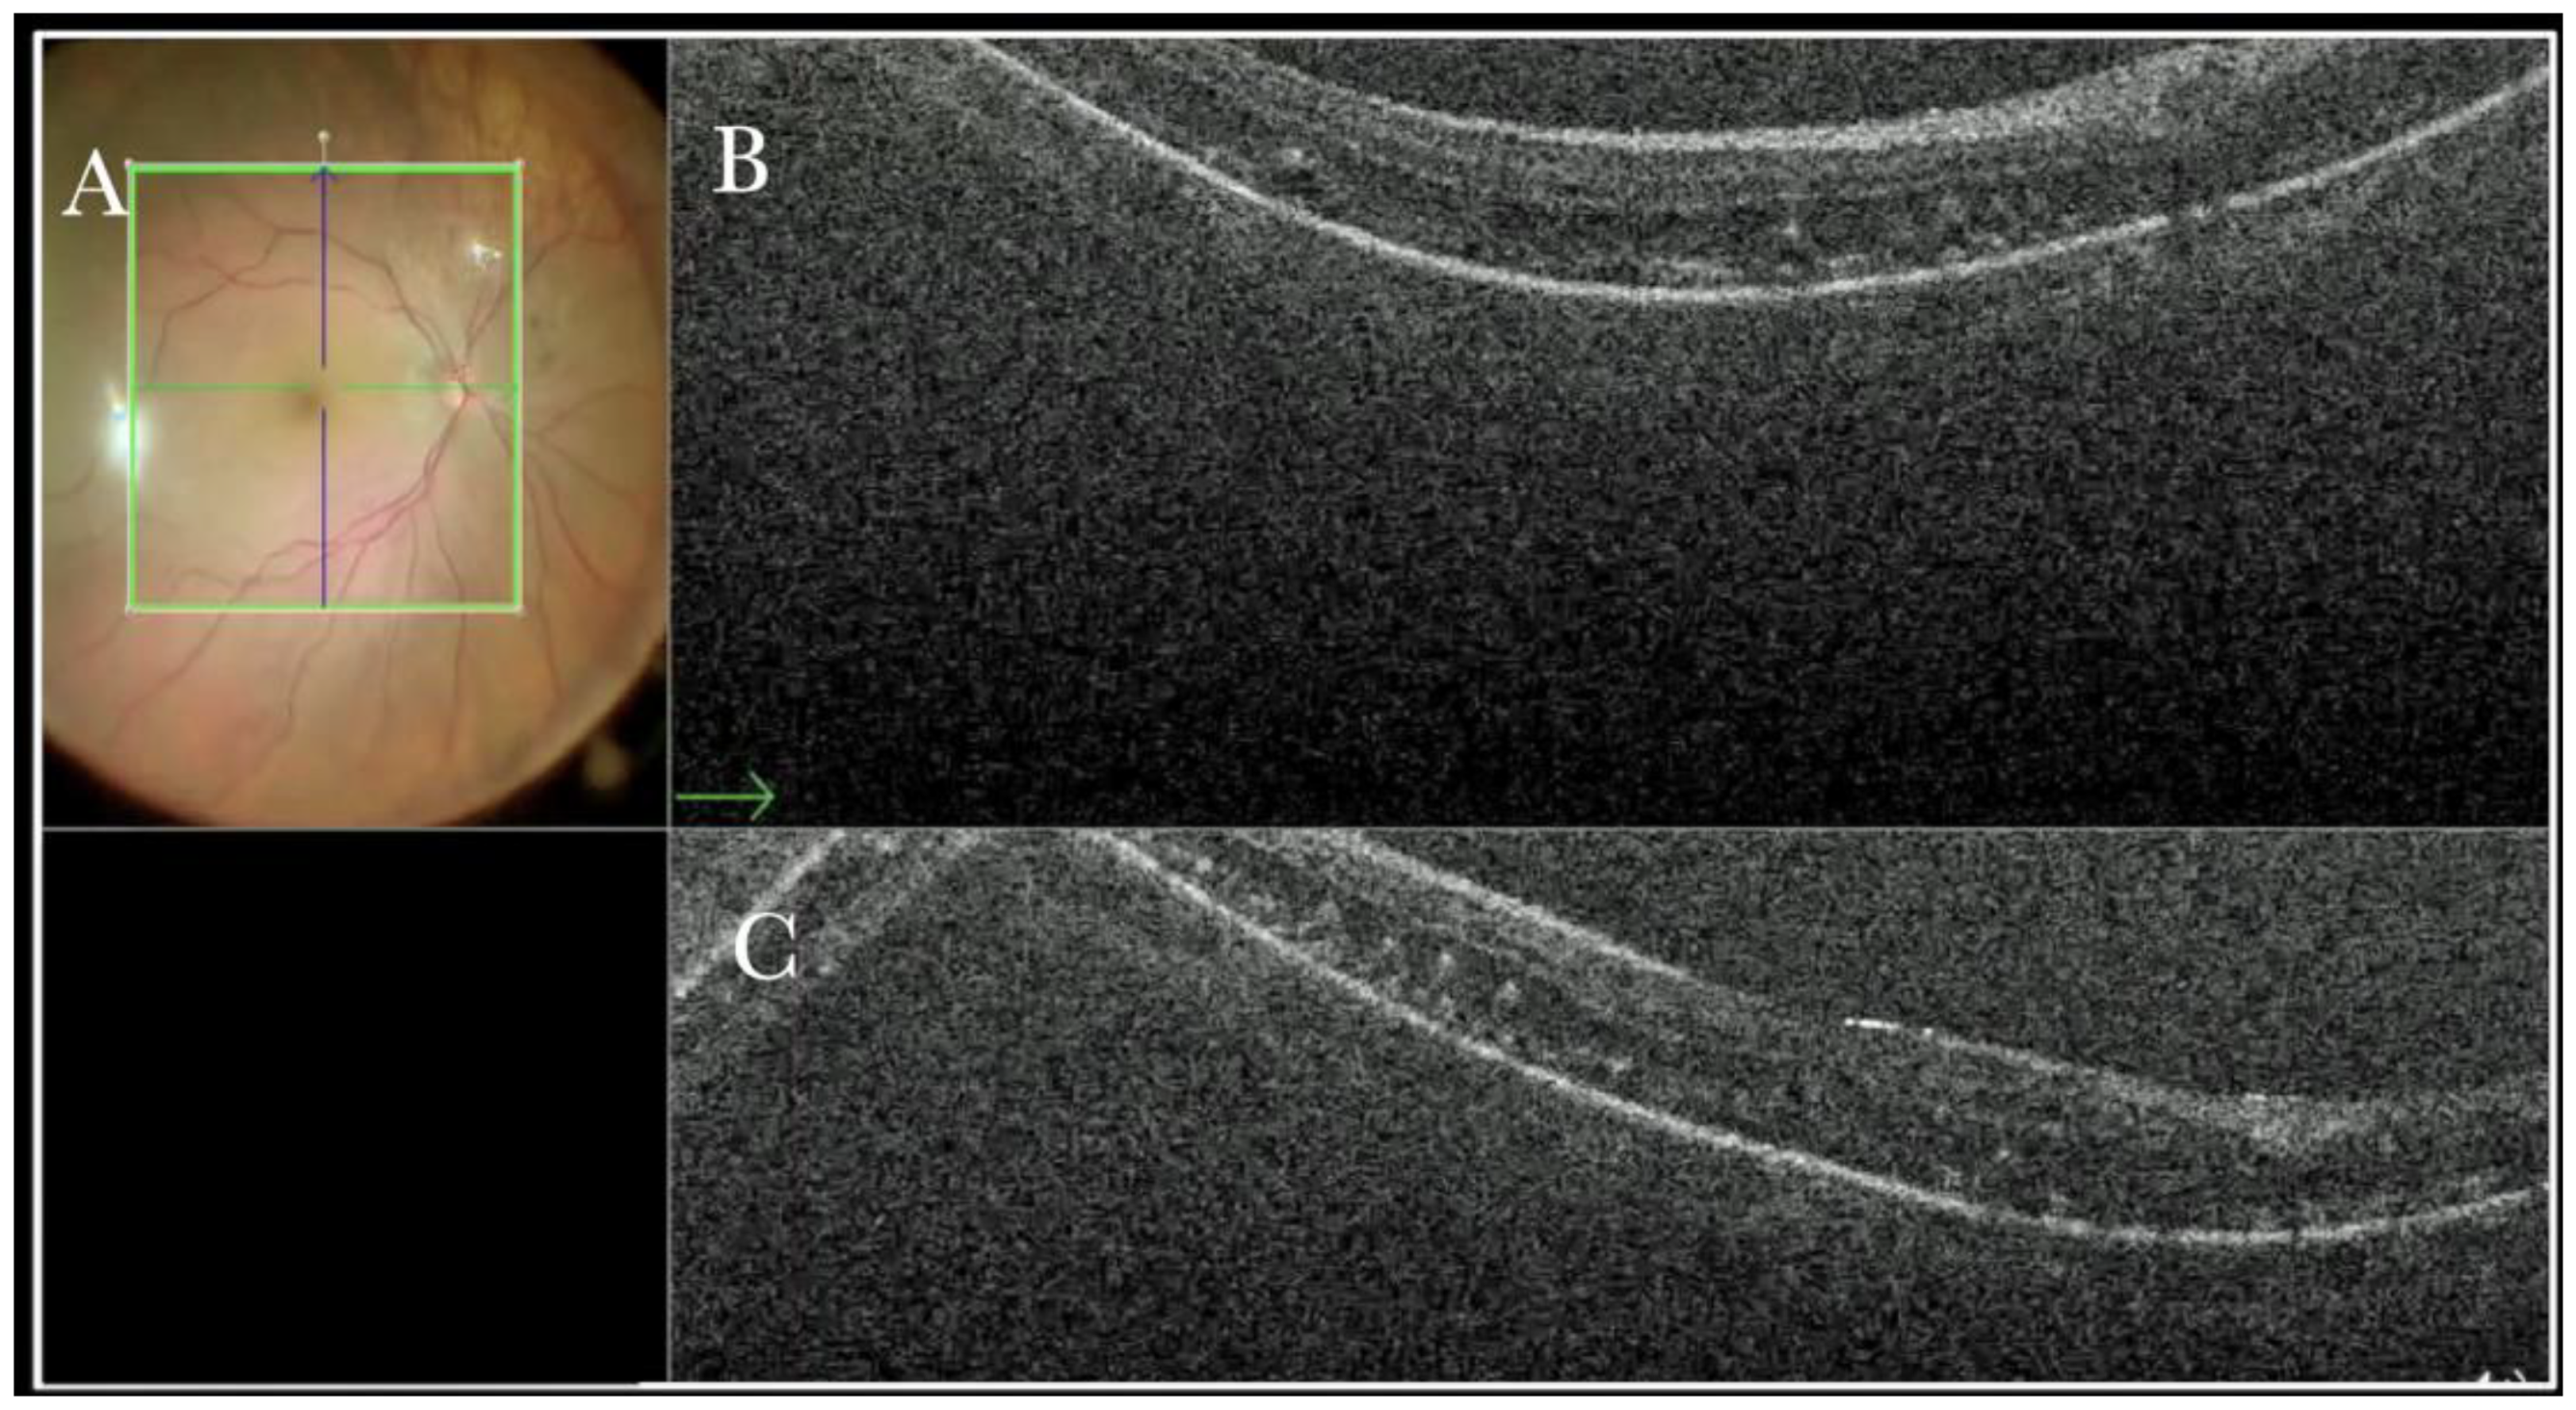

In primary ERMs, the i-OCT was as satisfactory as the dye staining in visualizing both the ERM (Figure 1) and the ILM (Figure 2), and enhancing well the visualization of the dynamic of the staining (Figure 3) and the membranes with architectural changes after the peel. The i-OCT was visualized when the ERM and the ILM were peeled simultaneously (Figure 4).

(A) Microscope view of the macular area with an epiretinal membrane (ERM) after staining with Doubledyne blue. (The white box indicates the field-of-view of the OCT scan, the green circle within the white box represents the effective working distance and green and blue lines within the green circle show the vertical and horizontal scan planes). (B) Intraoperative optical coherence tomography (i-OCT) B horizontal (green arrow) scan showing the macular profile after peeling and restaining with Doubledyne blue. (C) i-OCT B vertical (blue arrow) scan showing the macular profile after peeling and restaining with Doubledyne blue.

Figure 4.

(A) Microscope view of the macular area during peeling of an epiretinal membrane (ERM). The ERM is elevated. (The white box indicates the field-of-view of the OCT scan, the green circle within the white box represents the effective working distance and green and blue lines within the green circle show the vertical and horizontal scan planes). (B) Intraoperative optical coherence tomography (i-OCT) B horizontal (green arrow) scan during peeling. The ERM is elevated, and the macular profile is preserved where the ERM has been peeled. (C) i-OCT B vertical (blue arrow) scan during peeling. The ERM is elevated. The inner limiting membrane (ILM) is stretched and elevated where the ERM is peeled. The i-OCT allowed us to see the double simultaneous peeling of ERM and ILM.